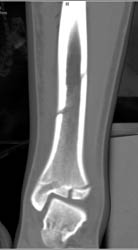

Failed Pectus Repair